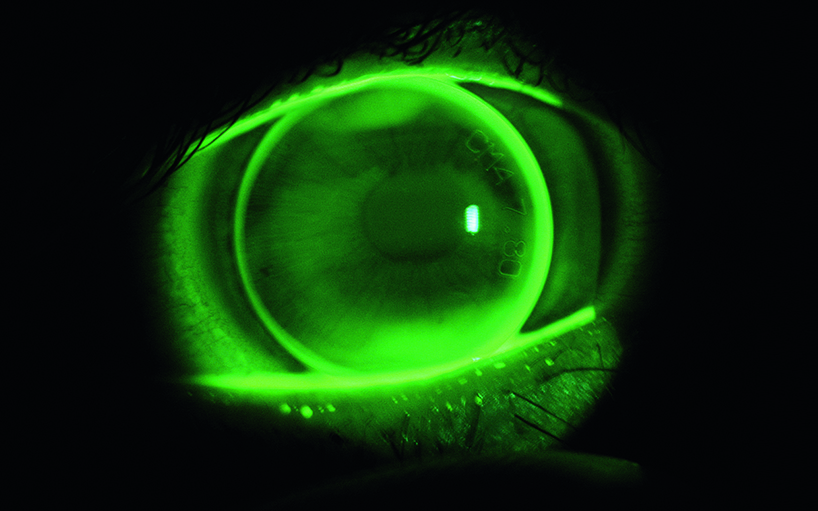

DCT-Lens

Développement d’une lentille de contact spéciale qui contient un capteur de pression pour la détermination de la pression oculaire.